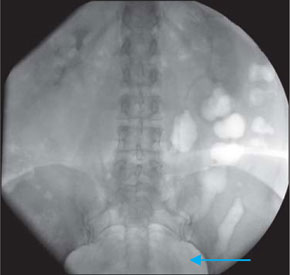

На обзорном снимке мочевых путей (рис. 3, 4) в проекции лоханки правой почки определяется тень, подозрительная на конкремент. На серии экскреторных урограмм чашечно-лоханочная система слева не расширена, дефектов наполнения в ней не выявлено. Пассаж контрастного вещества по мочевым путям не нарушен. Справа определяется расширение верхней чашечки до 14 мм, остальные отделы чашечно-лоханочной системы не расширены. Определяется дефект наполнения в лоханке правой почки, соответствующий тени конкремента. Пассаж контрастного вещества по мочевым путям сохранен.

Рис. 3. Обзорный снимок мочевой системы. Определяется тень камня в проекции лоханки правой почки до 2,5 см.